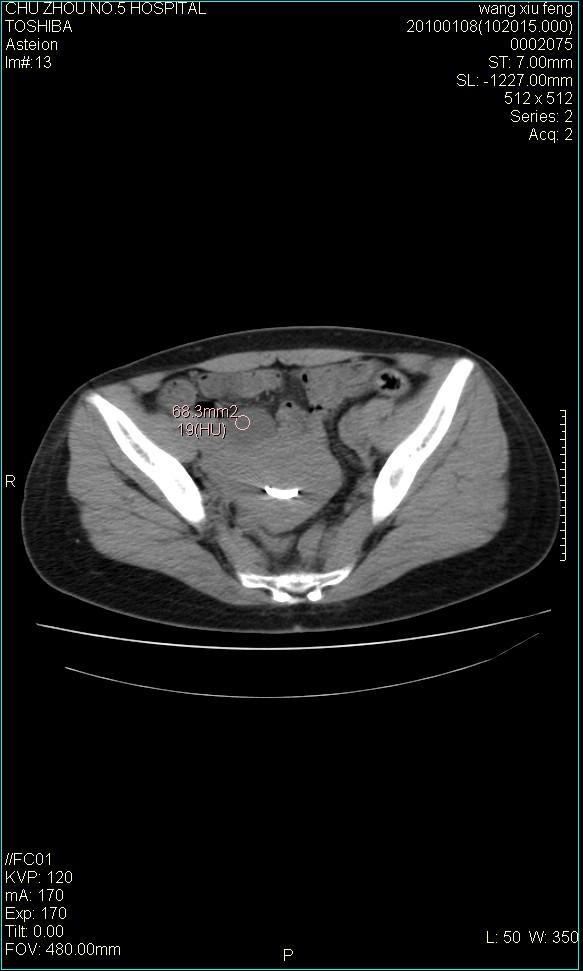

标题: CT24042:子宫右上方囊性包块,性质???? [打印本页]

标题: CT24042:子宫右上方囊性包块,性质????

f-41,左乳腺ca术后4年,b超示:子宫右上方囊性包块约5.5*3.4cm,前日行胸部ct平扫未见明显异常。

囊腺瘤,转移瘤不排除。

考虑右侧卵巢囊腺瘤?

右侧卵巢囊肿或小囊腺瘤。

考虑肠系膜囊肿可能性大

考虑右侧卵巢囊腺瘤?建议增强!

考虑右侧卵巢囊腺瘤。

考虑右侧卵巢囊性占位性病变(囊肿?囊腺瘤?)。